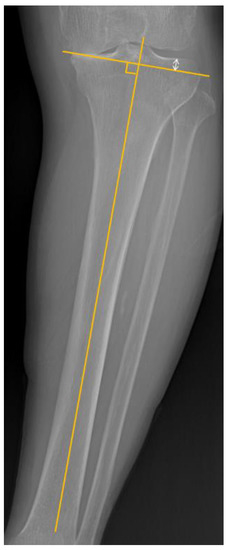

2.3. Pre-Operative Planning

2.4. Intraoperative Planning

| Proximal tibial reference point | |

| Center | 157 (71.4%) |

| In-between | 24 (10.9%) |

| Lateral tibial spine | 39 (17.7%) |